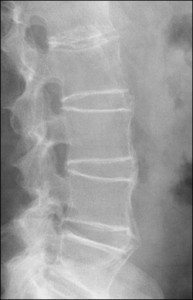

强直性脊柱炎(AS)是一种渐进的慢性炎症疾病,导致脊柱的总刚度和损失。作为一种影响脊柱的全身性,风湿性,渐进的慢性炎症疾病,比雌性更常见的男性(3:1)。确切的原因是遗骸未知但遗传和环境因素是[...]